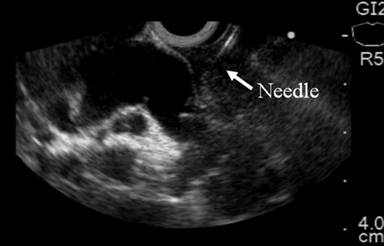

The common bile duct was visualized using a linear echoendoscope (GFUCT160, Olympus, Tokyo, Japan). Color Doppler US was used to identify the vascular anatomy. The dilated bile duct was punctured with a 19 gauge FNA needle (EUSN-19-T, Cook Endoscopy, Winston-Salem, NC, USA). The puncture position was chosen based on EUS evaluation, at the common bile duct above the tumor, through the distal part of the duodenal bulb (Figures 1 and 2).

Figure 2. EUS linear image demonstrating common bile duct puncture. |